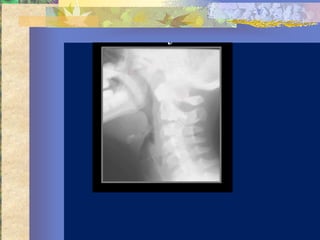

Diagnosis …. ?

Retropharyngeal

abscess

Abnormal retropharyngeal space:

    Retropharyngeal space :

>7 mm @ C2

    Retrotracheal space :

14 mm@ C6 .. Ped